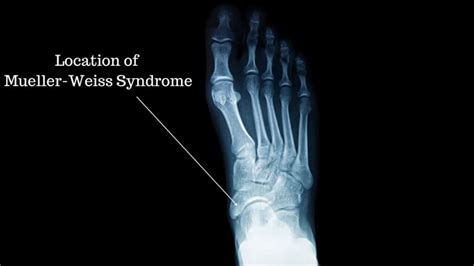

Learn about Mueller-Weiss syndrome, a rare degenerative condition affecting the navicular bone. Discover key symptoms, causes, and the latest treatment options, including orthotics, pain management, and surgical interventions. Understand how early diagnosis and expert podiatric care can help manage foot pain, improve mobility, and prevent long-term complications associated with this complex adult-onset foot disorder.